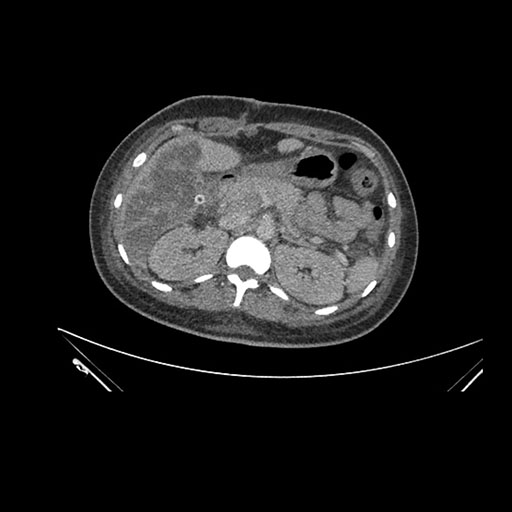

Imaging Analysis

Look through the patient's CT scan to identify any areas of concern for the necessary procedure.

Axial Arterial

Based on initial findings, which issue(s) would you be most concerned about?